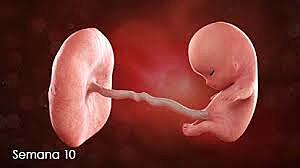

• semana 10

25

semana 10

su desarrollo deja patente que es un ser humano a simple vista a pesar de su minúsculo tamaño. Las medidas del bebé rondan los 4 centímetros y su peso los 5 gramos. A partir de ahora vamos a ver como crece a un ritmo de vértigo.